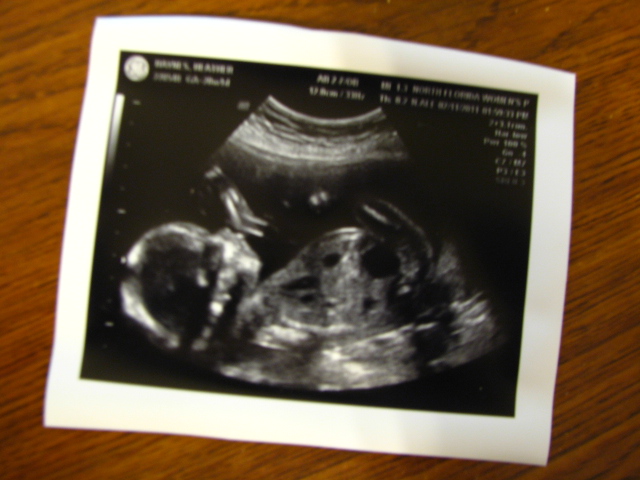

Today we had our first sonogram. It's a boy! Very excited.  The doctor's however have some concerns about our baby...some concerns with his heart and the umbilical cord.  We'll find out more after the blood work comes in.  Very exciting day!

- Aaron's Journal Entry